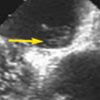

A subsequent transesophageal echocardiogram revealed a mobile mass of about 9 × 4 mm attached to the aortic valve (A). In addition, intravenous injection of agitated saline suggested a patent foramen ovale (PFO), with bubbles freely traversing the interatrial septum from right atrium to left atrium (B).

The patient underwent cardiothoracic surgery and excision of the mass. Pathological examination of the surgical specimen revealed a cardiac papillary fibroelastoma with multiple fronds (C). A PFO was not visualized during surgery; however, 2 tiny atrial septal defects, about 1 mm each, were closed by figure-8 suturing.